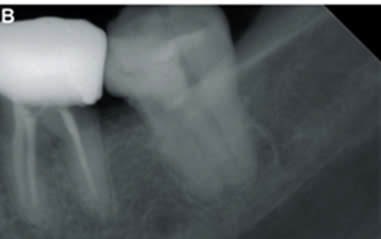

Hình 4: Xương ổ răng và nhú lợi vùng răng 37 bị hoại tử do arsenic7

Báo cáo những trường hợp lợi bị hoại tử do sử dụng arsenic băng thuốc trong buồng tủy thường liên quan tới những răng phải điều trị nội nha có tổn thương sâu mặt bên (xoang II).

Hình 5: Hình ảnh thiếu hổng xương sau khi phẫu thuật xương bị hoại tử do sử dụng arsenic trong điều trị nội nha răng 25 8.

Việc phẫu thuật cắt bỏ xương và răng bị hoại tử để lại thiếu hổng xương lớn gây khó khăn trong phục hồi lại răng mất cho bệnh nhân sau này. Đặt arsenic trong buồng tủy quá 3 ngày có thể gây các tác động xấu lên răng, xương ổ răng và lợi9